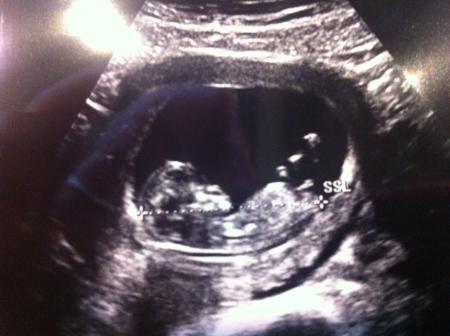

Ich Denk ma sie will nur vergleichen und schauen ob bei ihrem alles normal ist auch wenn der Arzt ein ok gegeben hat. Guck mir auch immer gerne Bilder an zum Vergleich. Also nicht immer gleich das schlimmste denken bitte. Bei dem Bild war ich in der 12 Woche

Bild zu

Denke sweety. Tolles Bild. Natürlich will ich nix böses bin selber bei den September Mama s nur wurde ich zurück gestuft.... 1 Woche.... Und wollte mal vergleichen. Weil ich eigentlich fand im Gegensatz zu vielen anderen wo bei mir im Monat weiter sind sah man bei mir mehr. Kann auch sein weil s einfach meins ist. Mein Bild ist von 5.2 da war er 27 mm groß. Eigentlich wäre ich 11+5 bin aber nun 10+5